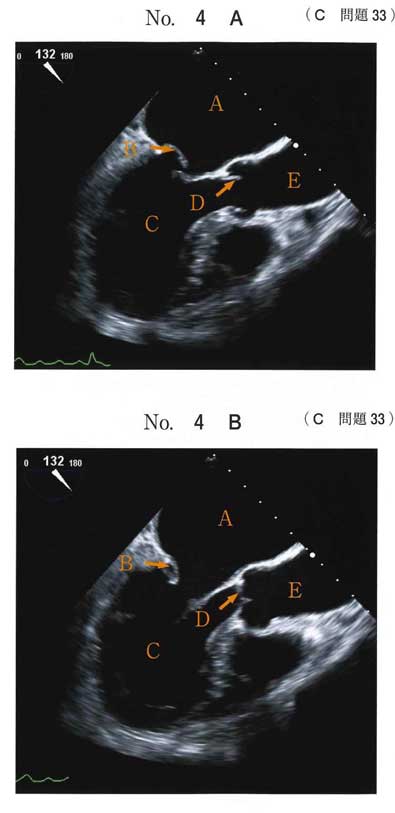

bc LAが、最も後ろ(食道側)にあることを知っていれば経食エコー画像見たことなくてもなんとかなりそう